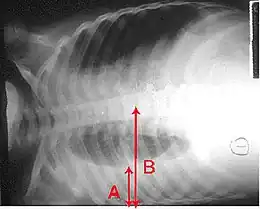

Épanchement pleural droit